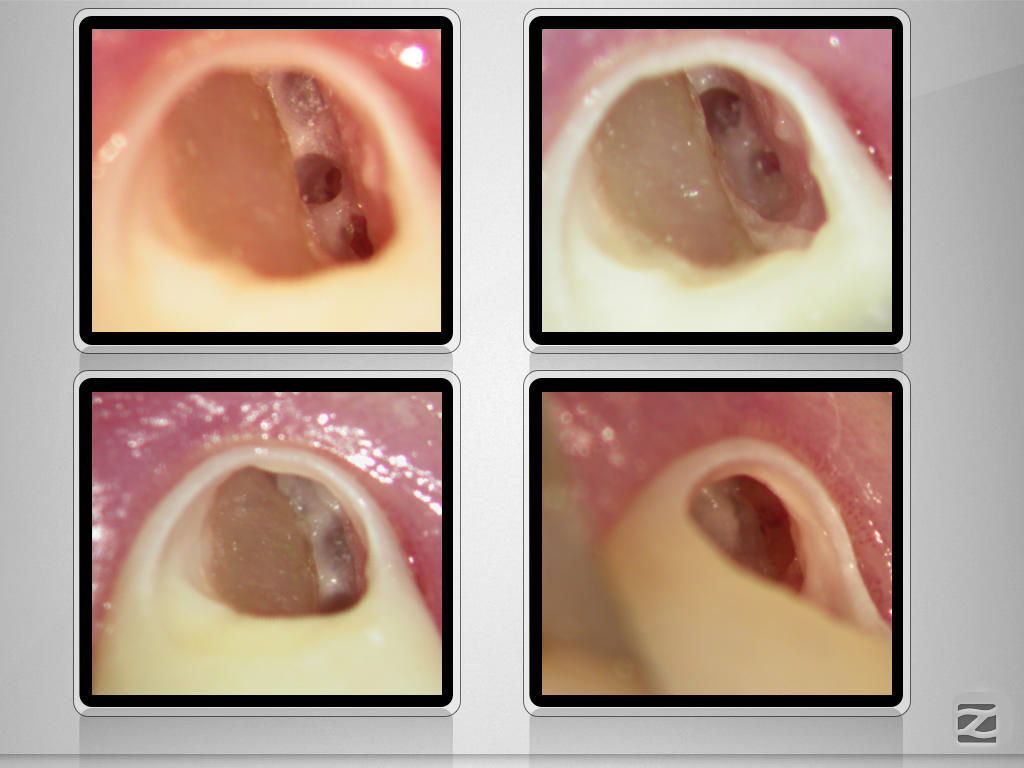

Externe Resorption mit Perforationen